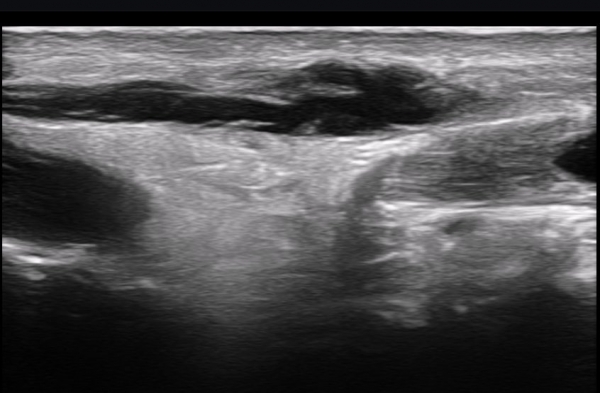

ÃÊÀ½ÆÄ ¼Ò°ß : ºñº¹½Å°æ Ⱦ´Ü¸é°Ë»ç¿¡¼­(»çÁø 1~13) ºñº¹½Å°æÀÇ Àú¿¡ÄÚ ºÎÁ¾°ú ´Üºñ°ñ°Ç³» ³¶Á¾¼º º´º¯ÀÌ °üÂûµÈ´Ù.

ºñº¹½Å°æ Á¾´Ü¸é°Ë»ç(»çÁø 14, 15)¿¡¼­ ºñº¹½Å°æÀÇ Àü¹ÝÀûÀÎ Àú¿¡ÄÚ ºÎÁ¾°ú ºñº¹½Å°æ ½ÉÃþÀ¸·Î ´Üºñ°ñ°Ç³»

³¶Á¾¼º º¯º¯ÀÌ °üÂûµÈ´Ù.